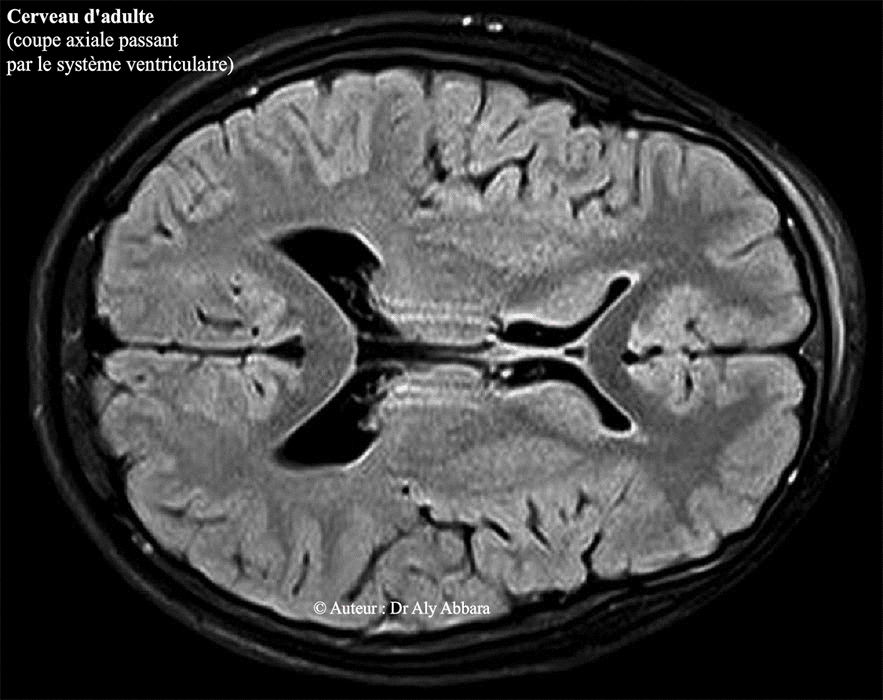

Cerveau d'adulte - coupe axiale passant par le système ventriculaire du cerveau (les ventricules latéraux et le 3° ventricule) - Image d'IRM

Voir : coupe axiale 2 ; coupe sagittale médiane